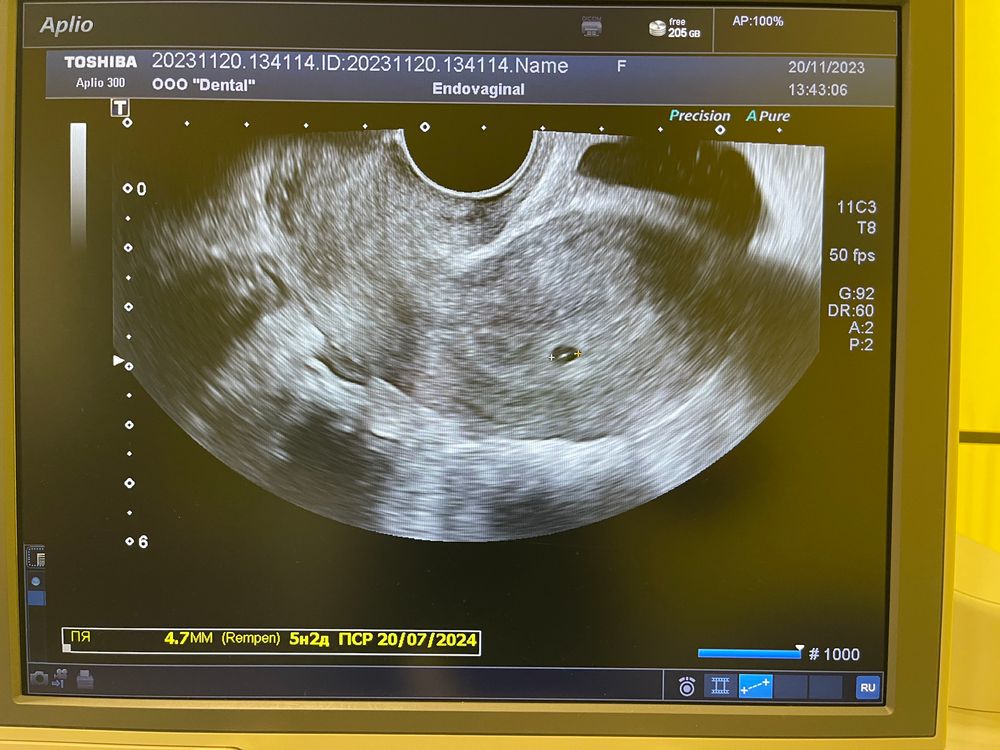

УЗИ 5 Нед 2 дня акушерские, плодное яйцо двигалось вперед назад при осмотре, ставят угрозу. Точно ли

Подскажите какой размер пя поставили?)

Валентина, 4,7 мм